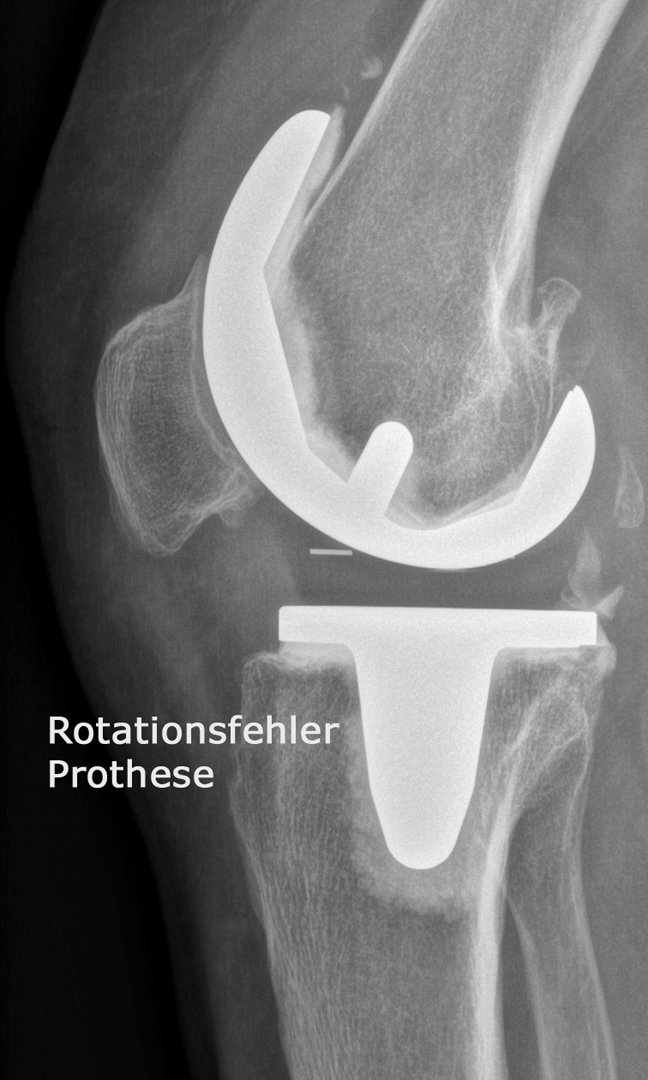

Welcher Typ einer Knieprothese für die Behandlung der Kniegelenksarthrose verwendet wird hängt neben dem Patientenalter vorwiegend davon ab, welche Teile des Gelenks abgenützt sind. So können bei isolierten Abnützungen des inneren Gelenksteils sogenannte Schlittenprothesen ( linkes Bild) und bei Abnützungen des gesamten Gelenks Totalprothesen  (mittleres Bild) eingesetzt werden: In besonders schweren Fällen von Fehlstellung in Kombination mit fehlender oder unzureichender Bandstabilität werden auch immer wieder sogenannte achsegeführte oder gekoppelte Prothesenmodelle (rechtes Bild) eingesetzt.